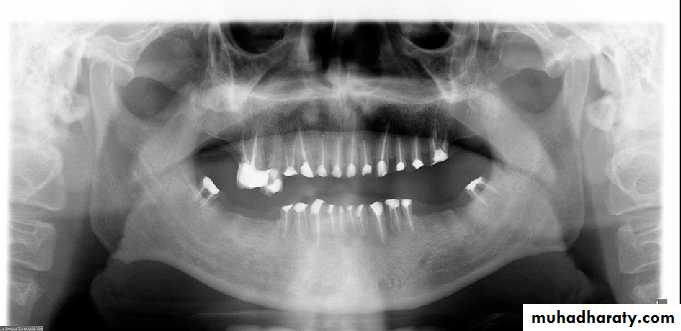

Panoramic radiography also represents a 2-D image of 3-D anatomy that again has some limitations It also contains artifacts and unique distortions that can further complicate panoramic interpretation.